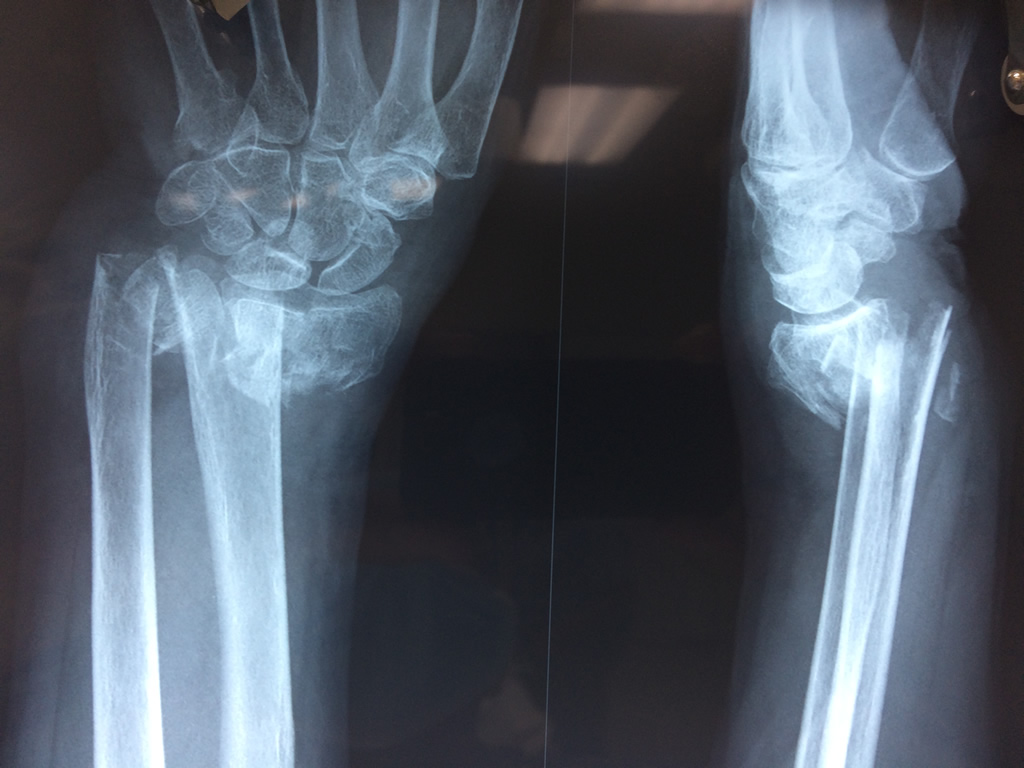

Cirugías de Codos - Cirugías de Muñecas y Manos

Los procedimientos más comunes en cirugía de la mano son aquellos destinados a reparar traumatismos, incluyendo lesiones de tendones, nervios, vasos sanguíneos, y articulaciones; huesos fracturados; y quemaduras, cortes, y otros daños de la piel.